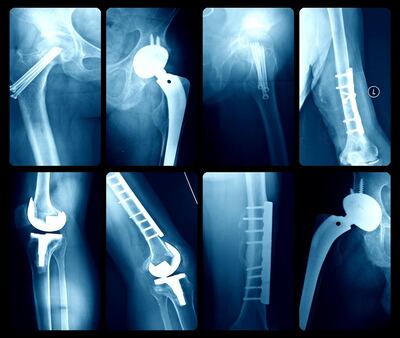

In the region of 10,000 hip and knee replacements are carried out in Ireland every year. Recovery times post surgery have reduced dramatically, with hospital discharge after three to five days now the norm.

For those offered elective joint replacement a big question is: how long will my new joint last? Leaving aside postoperative complications, such as bleeding, infection or dislocation, nearly every patient offered a new hip or knee wants to know the likely life-span of a new joint.

The aim of knee replacement surgery is the long-term relief of pain and restoration of function. However, knee replacements may fail for a variety of reasons, including loosening, infection, persistent pain and instability, and so might require revision. But revision is expensive and the outcome is worse than first-time knee replacement.

The answer produced a surprisingly optimistic result: some 82 per cent of total knee replacements (TKRs) last 25 years. In other words, if you have a TKR aged 65 you have an 8 in 10 chance of the new joint lasting until you are 90.

The same team of researchers repeated the study but this time for total hip replacements (THR). The typical patient who had a hip replacement in the UK in 2016 was a 70-year-old woman or a 68-year-old man. Some 90 per cent of hip replacements were carried out for osteoarthritis and 60 per cent of recipients were female.

Due to the poor quality of studies identified in the systematic review, the researchers findings on hips are less certain than for TKR. “Although there is not enough information yet available to calculate exactly how long a hip replacement will last ...we estimate that about three-quarters of hip replacements last 15-20 years and just over half of hip replacements last 25 years in patients with osteoarthritis”, they conclude.